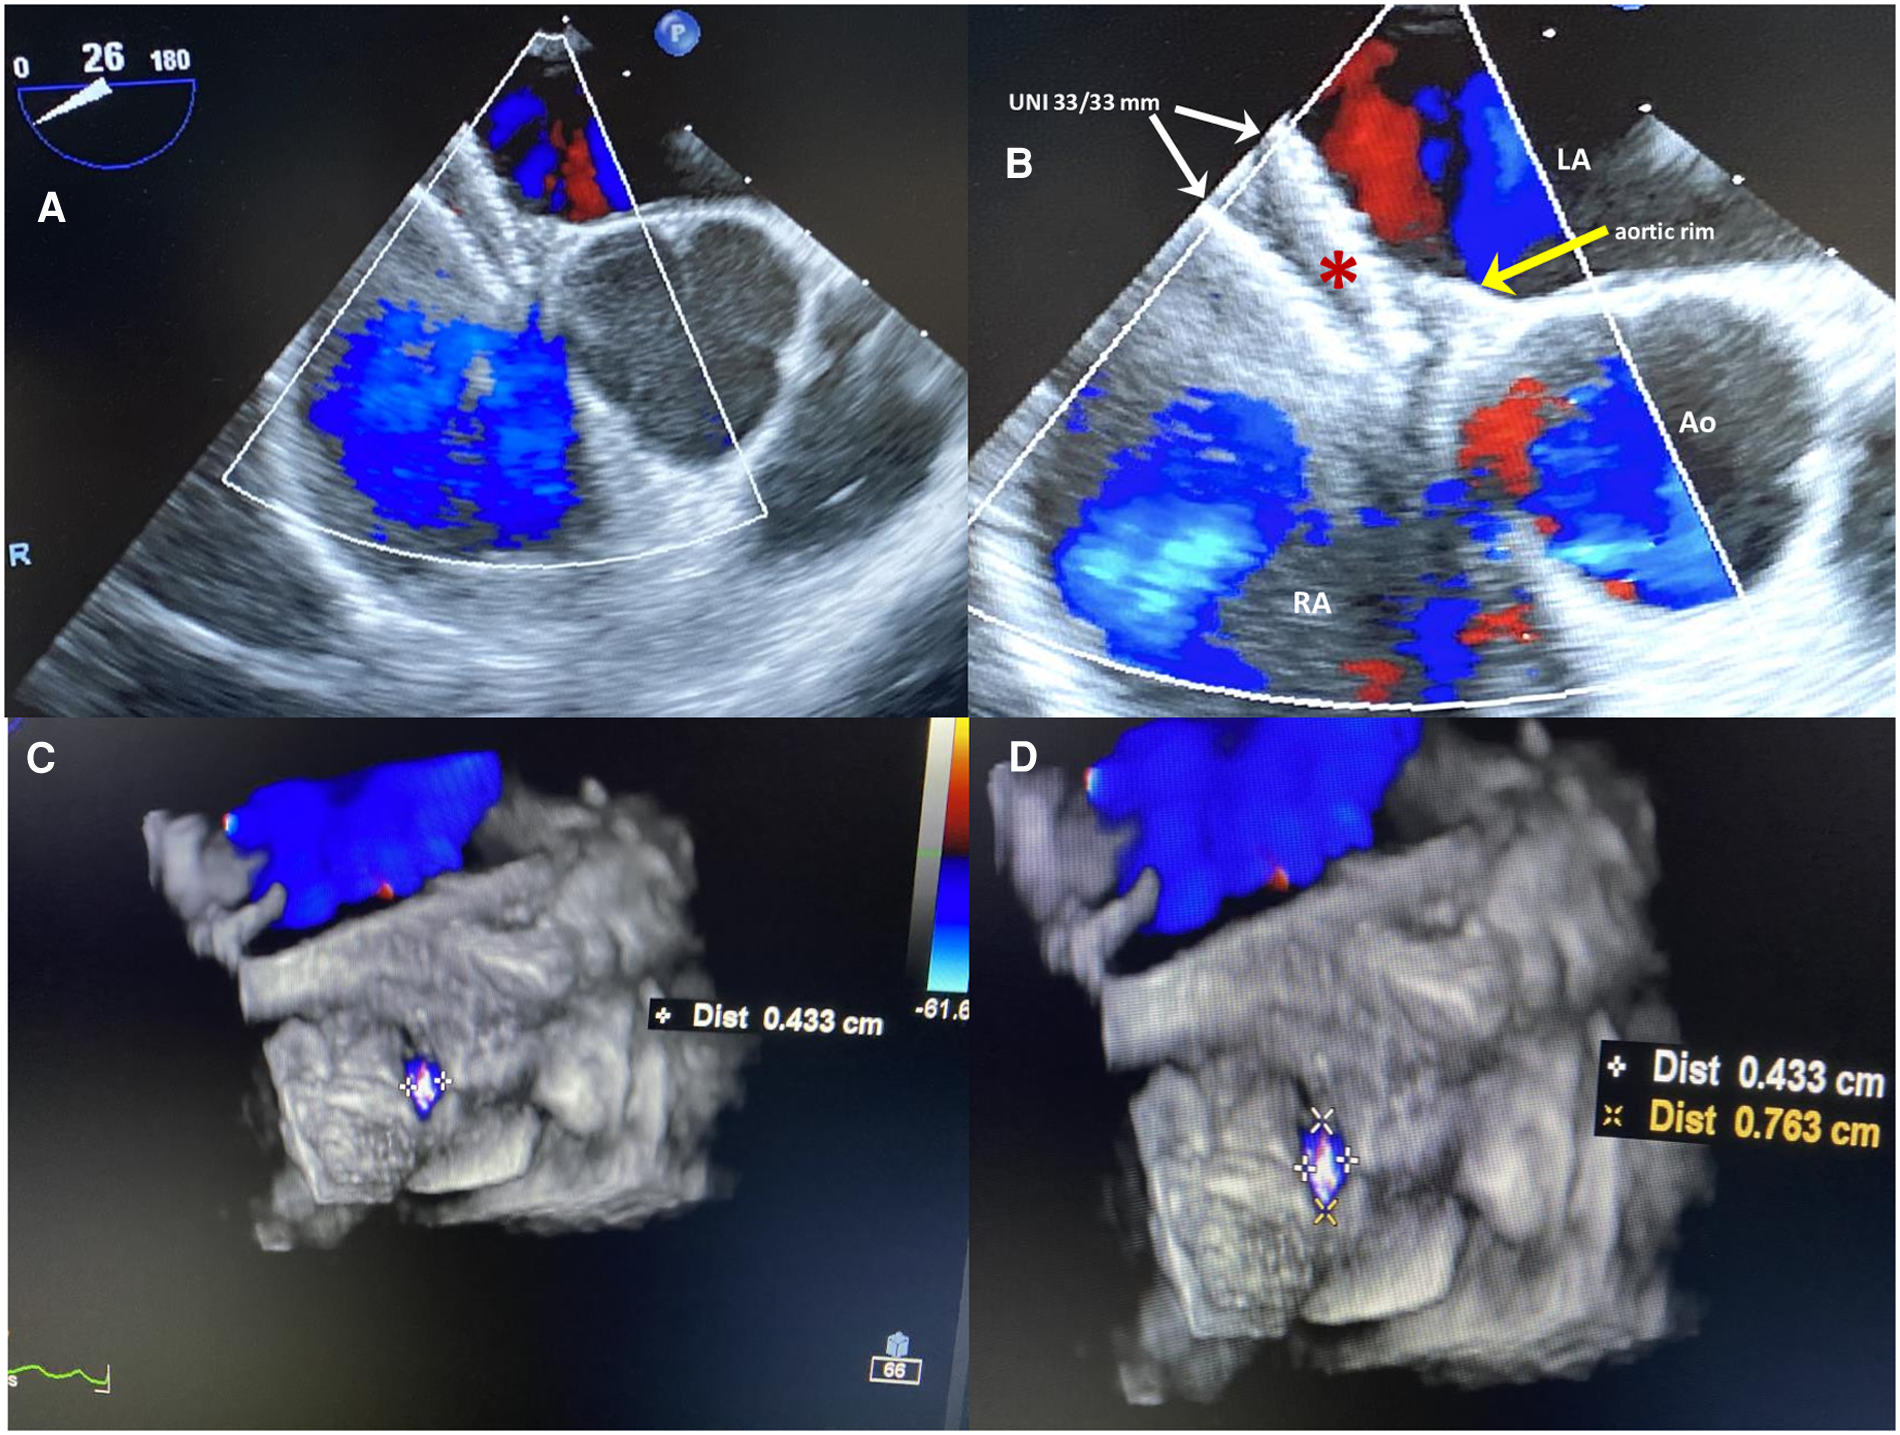

Although the indication was not supported by the guidelines (11, 12), transcatheter PFO closure was performed at another center with the implantation of a large, equally sized, double-disc device, Figulla UNI 33/33 mm (Occlutech International AB, Helsinborg, Sweden). The patient was discharged home on dual antiplatelet therapy (aspirin 100 mg and clopidogrel 75 mg daily) for 6 months. At 6 months follow-up, 2D/3D transesophageal echocardiography (TEE) color Doppler showed incorrect orientation of the device, not parallel to the interatrial septum, with the two discs not capturing the aortic muscular rim and partially protruding in the right atrium (Figures 1A,B); furthermore, a 4 mm × 7 mm ASA fenestration (septal defect) far from the UNI device was also identified (Figures 1C,D), with a residual bidirectional shunt that persisted unaltered on subsequent controls. Eight months later, the same team performed a minimally invasive cardiac surgery (MICS) procedure on the patient using a right parasternal approach under femoro-femoral cardiopulmonary bypass, which failed to close the residual shunt with interrupted sutures, ultimately leaving the inappropriately oriented device in situ. Regrettably, surgery proved not only ineffective but also complicated by postoperative pericarditis with pericardial effusion, which prolonged hospital stay. One month later, the patient was re-hospitalized due to persistent pericarditis, bilateral pleuritis, phrenic nerve palsy, and atrial flutter and was treated with amiodarone. Thereafter, colchicine and high doses of prednisone were used to treat and prevent recurrent pericarditis.

Figure 1

(A,B) Six-months 2D TEE color Doppler in the short view after the first percutaneous PFO closure procedure. The large equally sized double-disc UNI 33/33 mm device (red asterisk), is not parallel to the interatrial septum, with two discs diverging on one side (white arrows) and on the other side not capturing the aortic muscular rim (yellow arrow); the device is partially protruding in the right atrium with inappropriate orientation. (C,D) 3D TEE color Doppler showing a 4 mm × 7 mm ASA fenestration (septal defect) far from the UNI device.